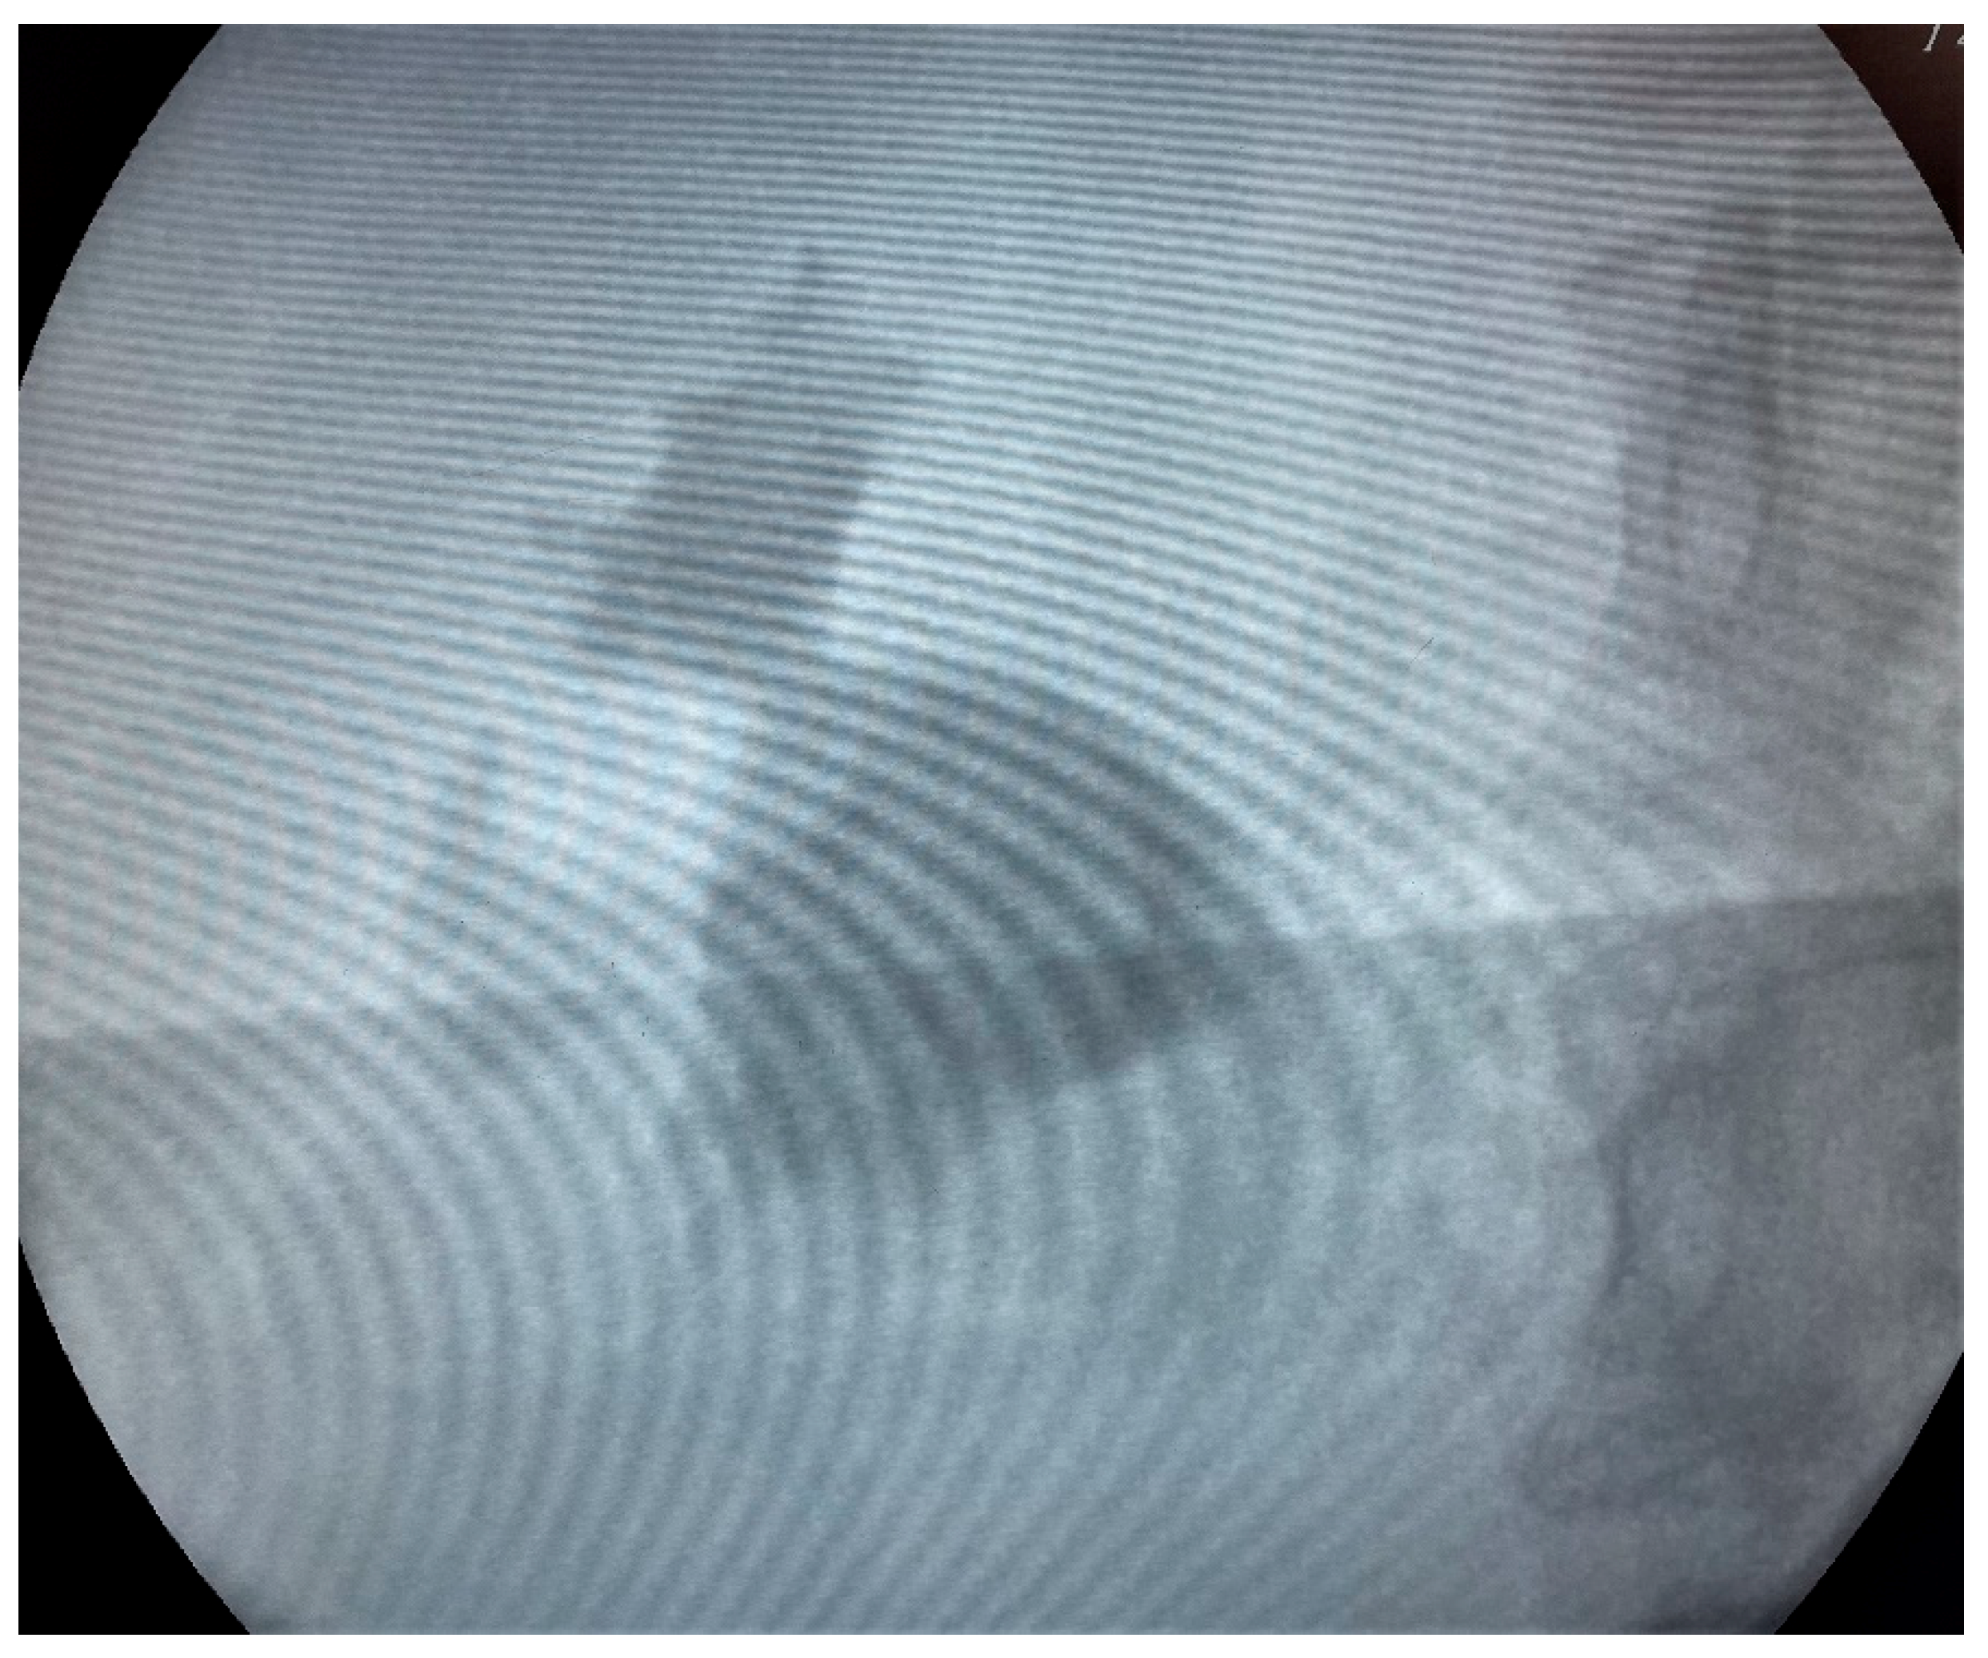

We proceeded with our standardized protocol of RIRS. Under general anesthesia, the patient was placed in the lithotomy position. At first, we performed a cystoscopy of the bladder. We found the right ureteral orifice and placed an ureteral catheter. Via the catheter, contrast agent was infused and, under fluoroscopy, the renal collecting system and the calculi was detected (Figure 1). The insertion of the guidewire followed, an ureteral access sheath was placed and through it we reached the kidney with a flexible ureteroscope of 8.6 French. The stones were found in the upper calyx and in the pelvis (Figure 2) so we began lithotripsy using holmium laser, checking throughout the whole procedure with fluoroscopy. In the meantime, the contrast agent was almost eliminated from the pelvicalyceal system and the stones were efficiently exported. Although we could not see any other calculi in the system, in the fluoroscopy there seemed to be one more (Figure 3). Therefore, we continued our endoscopy in order to find it. We came up to a small aperture in the spot that was indicated to us by the fluoroscopy, so we diagnosed an infundibulum stenosis and thought that the calculi would be within the calyx. The ureteroscope could not be inserted due to the stenosis, so we used the laser to widen the aperture. When the bore was opened and the access to the calyx was provided (Figure 4) we still could not found any calculi. In the fluoroscopy the sign has disappeared (Figure 5) so we understood that the contrast agent was entrapped in the calyx mimicking a stone in the fluoroscopy. The patient was stone free. We placed a double-J stent according to our protocol and the operation has ended. The patient the next day was free to leave the hospital without any complications, according to Clavien–Dildo system.

Figure 1. Fluoroscopy image of the pelvicalyceal system showing the stone.